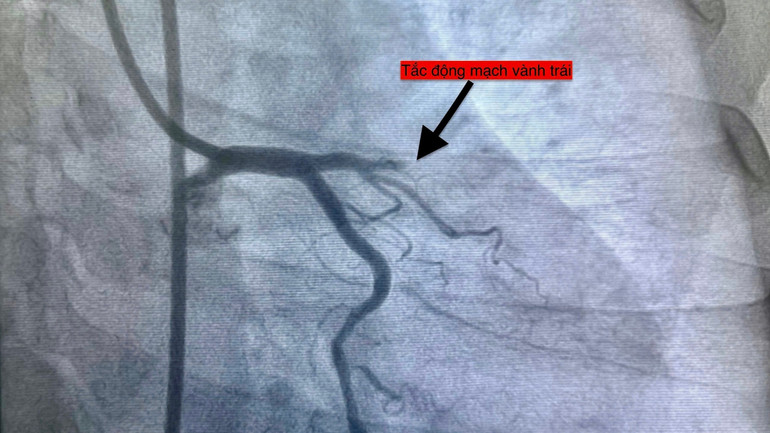

| Hình ảnh chụp các ca bệnh nhồi máu cơ tim. |

Đây là điều kiện dễ gây rối loạn điều hòa mạch máu, làm tăng huyết áp, tăng độ nhớt máu và hoạt tính tiểu cầu là những yếu tố then chốt kích hoạt huyết khối trong động mạch vành.